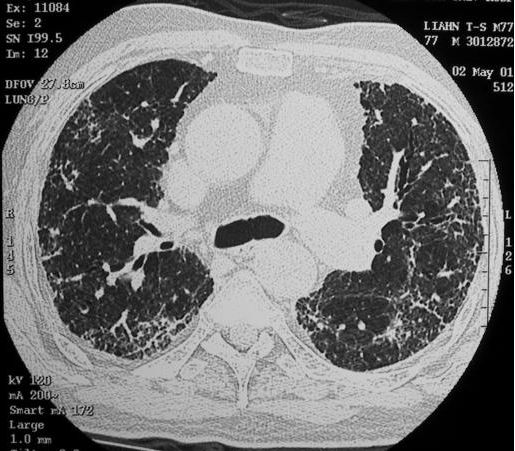

11. 一位66歲男性,主訴呼吸困難有二個月,胸部影像如圖(圖a,圖b)。他的肺功能檢查結果可能顯示何種變化?

1. VC正常或↑ , 2. RV ↑ , 3. RV/ TLC ↓ , 4. FEV1 / FVC 正常或↑ , 5. DLco ↓

圖a

圖b

(A) 1 + 3 (B) 1 + 4 (C) 2 + 4 (D) 2 + 5 (E) 4 + 5